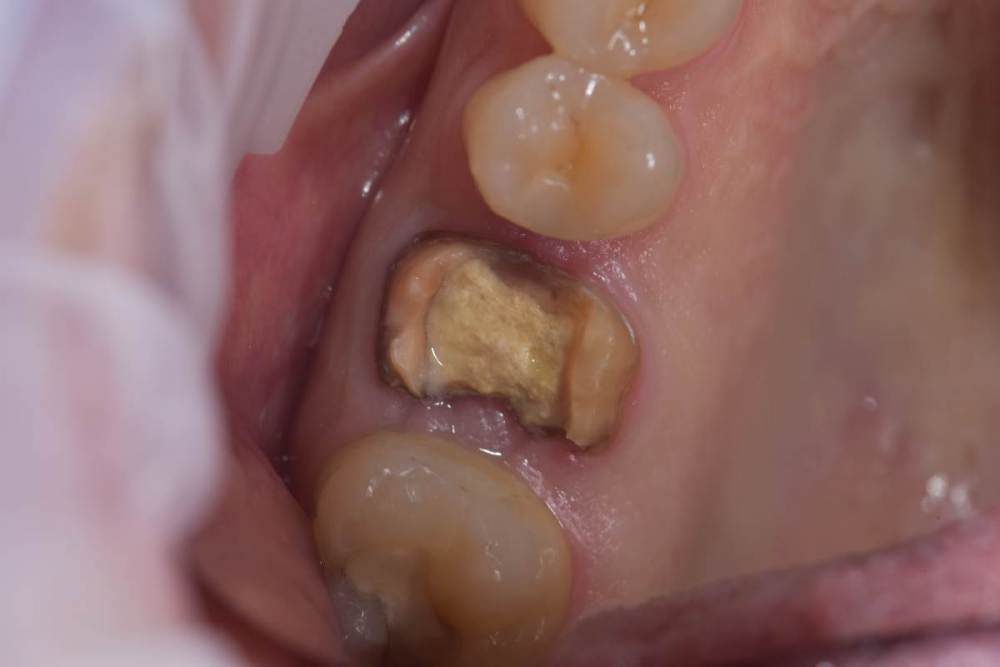

TIGER Опубликовано 4 февраля, 2022 Поделиться Опубликовано 4 февраля, 2022 (изменено) Видео отслойки мембраныКоллеги доброго дня!Вашему вниманию закрытый синус-лифт под визульным контролем через операционный микроскоп)С появлением скопа в практике стало больше закрытых синусов)остальные методы не позволяют контролировать операционное поле при отслоение мембраны (на видео ниже запечатлена отслойка) MAH01810.MP4 Изменено 4 февраля, 2022 пользователем TIGER 3 1 Ссылка на комментарий